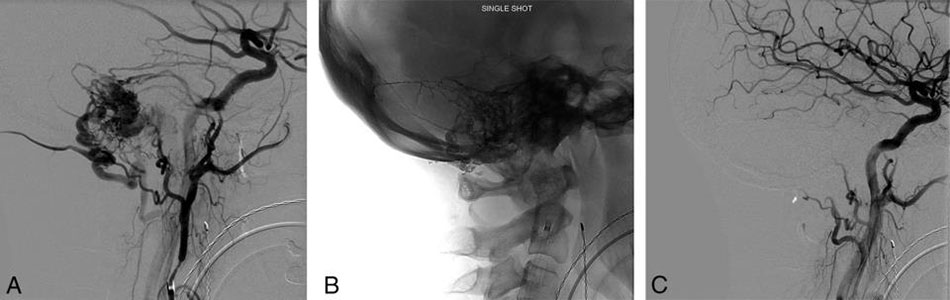

Endovascular Neurosurgery

This is a radiology procedure that looks at how blood is flowing in the brain.

Conditions such as cerebral aneurysms, vascular malformations, vascular tumours, strokes and stroke related symptoms can be diagnosed with a cerebral angiogram

Arteriovenous malformations (AVM)

Arteriovenous malformations are abnormal collections of blood vessels, where arteries are directly connected to veins. Normally blood flows through arteries under high pressure to supply all of the organs of the body including the brain. From the arteries, blood passes through thin-walled capillaries to supply oxygen and nutrients to the tissue of the brain and then enters the veins under low pressure to be carried back to the heart and lungs.

In an AVM, the blood flows from the arteries directly to the veins. There is no capillary bed. Without a capillary bed, the AVM blood vessels have an increase in flow and blood pressure. Over the years this causes them to dilate and become thin-walled, and more likely to break and bleed.

An AVM can cause headache, weakness, numbness, visual problems, or seizures. Patients often first show symptoms when there is a bleed or rupture from one of the blood vessels making up the AVM.

An AVM is often diagnosed with a CT scan or MRI. A patient usually requires an angiography to then fully identify the anatomy of the AVM and make decisions about treatment.

AVMs may be treated using three different treatment methods. These methods are embolization, surgery and radiation therapy or radiosurgery.

Endovascular treatment of AVMsis available at FV Hospital. One innovative form of treatment involves use of a “super glue” substance introduced via a tiny catheter to reduce the size of the AVM and facilitate further microsurgical or radiation treatment. In some cases, it is possible to completely block off and cure the AVM with endovascular treatment alone.